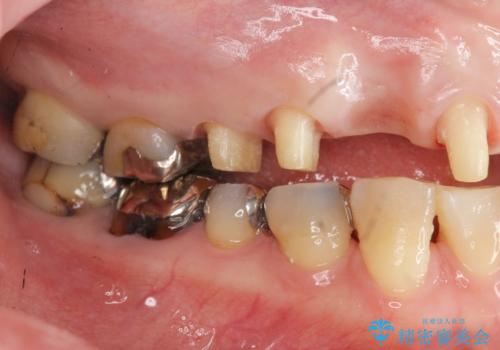

- 前歯を噛みしめにより失い、さらに犬歯もグラグラになり全く噛めなくなり改善を求めて来院されました。

過度な力がかかり周囲の骨に高度な吸収が見られた犬歯は抜歯し、機能・審美性の回復をより咬合力に対して抵抗力のあるブリッジ補綴にて対応します。